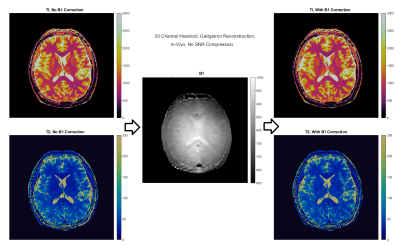

In Figure 3, the impact of the implemented online B1 correction method is demonstrated for in-vivo acquisitions, with inclusion of B1 mapping data in the online reconstruction yielding visible correction in T2 maps, with no change in reconstruction time.

In-Vivo quantitative maps demonstrating the pipeline's ability to perform online B1 correction as a B1 prescan is completed during the same acquisition and was forwarded to the Kubernetes cluster.